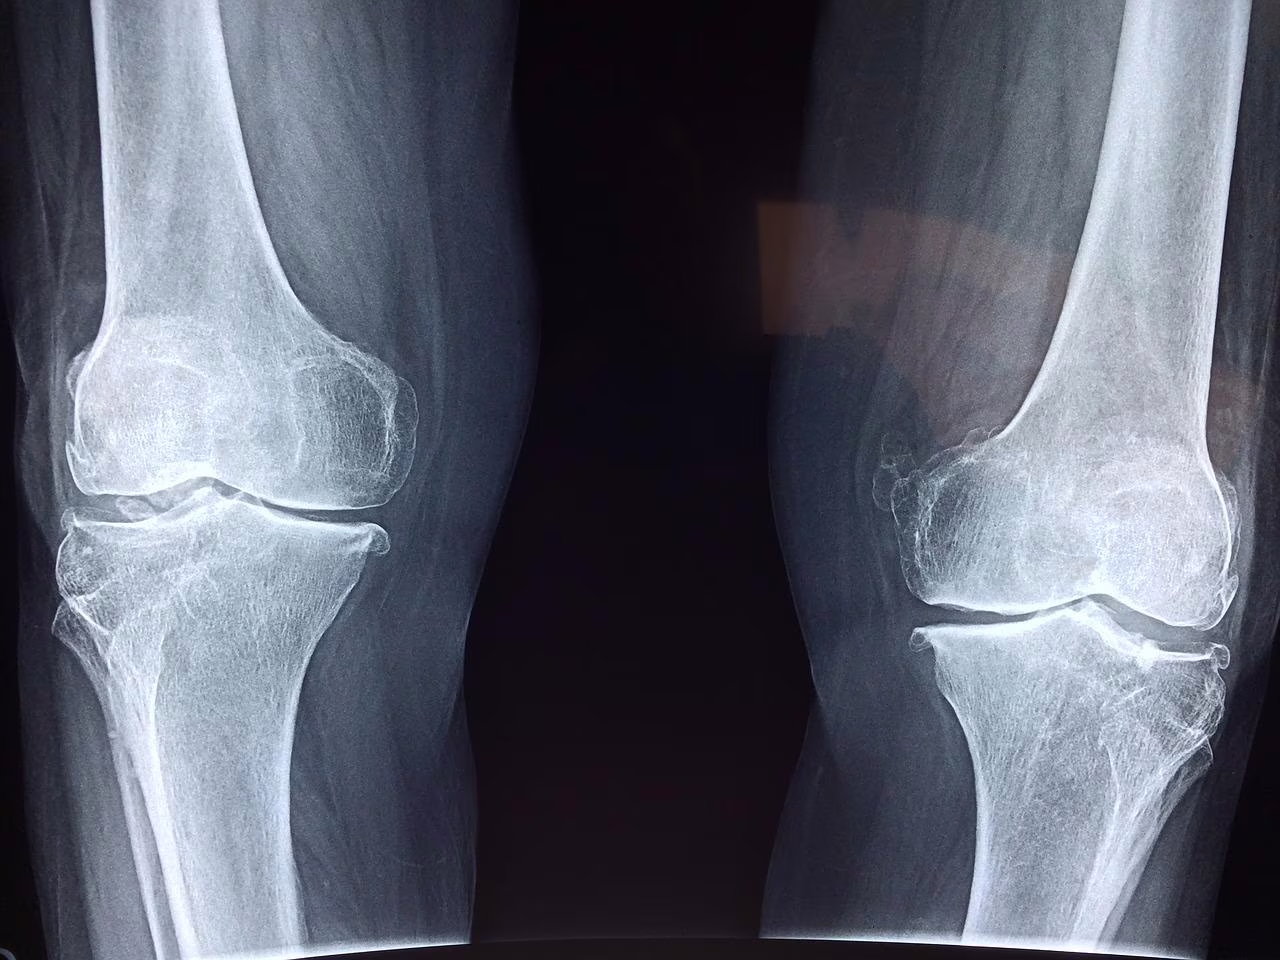

Le lesioni più comuni nelle persone che soffrono di questa patologia sono: polso rotto, anca rotta, ossa spinali rotte (vertebre) e problematiche alle ginocchia. Tuttavia, le rotture possono verificarsi anche in altre ossa, come nel braccio o nel bacino. A volte, un episodio di tosse o starnuti può causare la rottura di una costola o il collasso parziale di una delle ossa della colonna vertebrale.